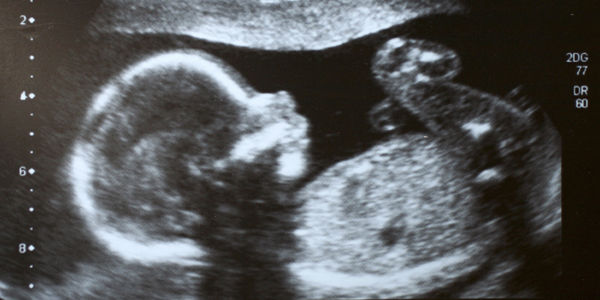

La Procréation Médicalement Assistée (PMA) est un droit réservé aux couples hétérosexuels dont l’extension aux couples de femmes vient d’être enterrée par le gouvernement

La Procréation Médicalement Assistée (PMA) est un droit réservé aux couples hétérosexuels dont l’extension aux couples de femmes vient d’être enterrée par le gouvernement. Ce renoncement est un coup porté au droit des femmes et à l’égalité entre les couples homosexuels et hétérosexuels.